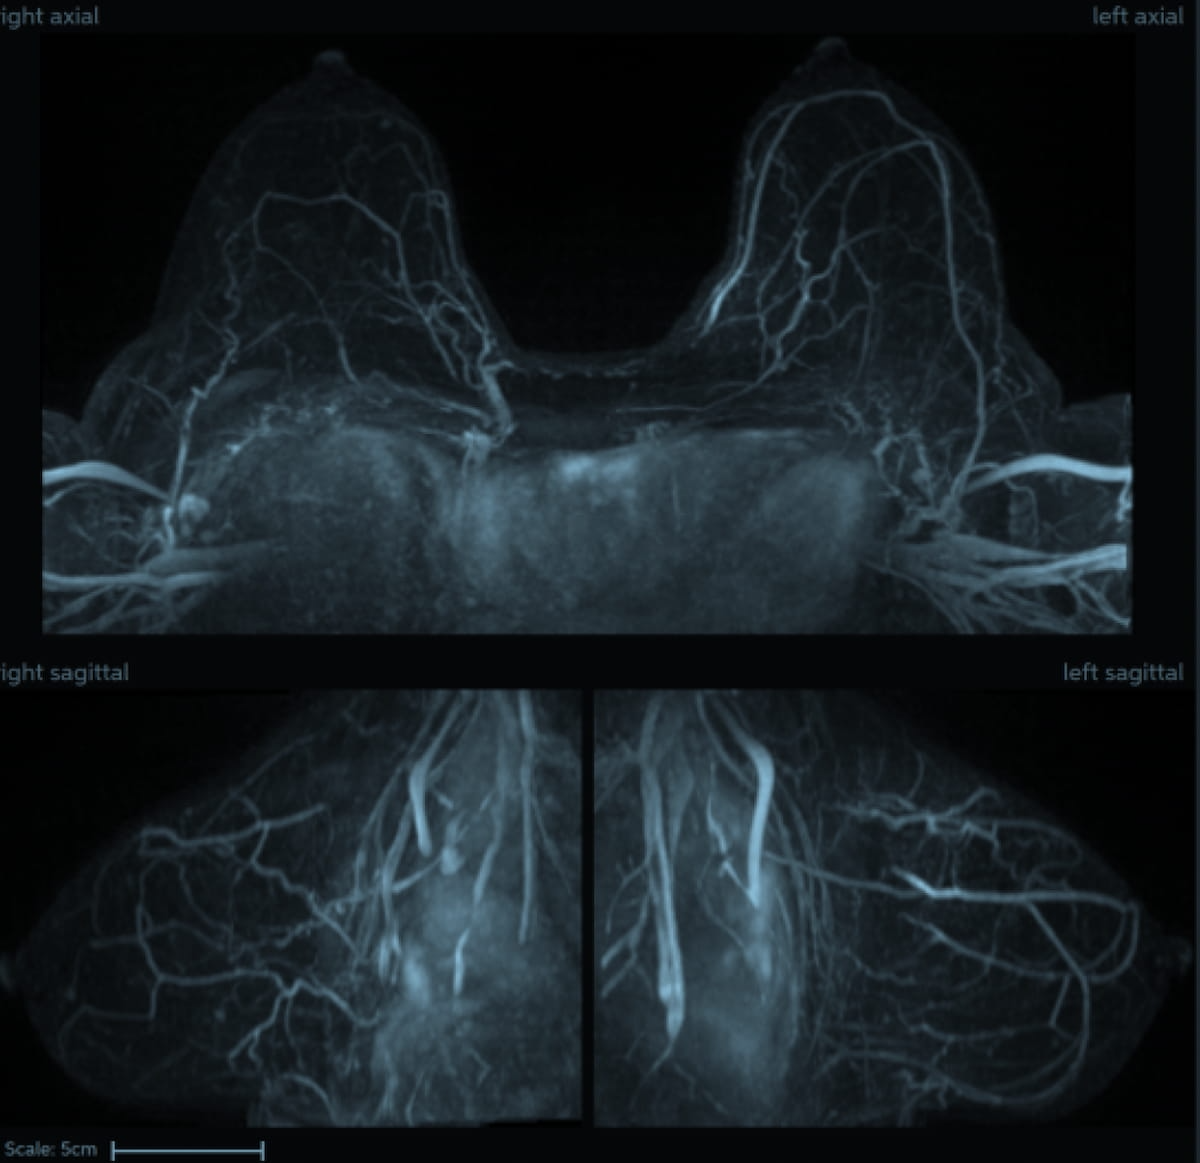

LOS ANGELES — An MRI exam on the left shoulder of Los Angeles Dodgers left-hander Blake Snell revealed no structural damage, manager Dave Roberts said Friday. The two-time Cy Young Award winner hasn't pitched for his new team since April 2 due to left …